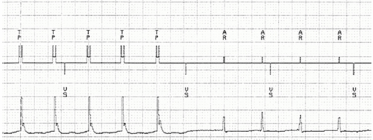

Um paciente de 62 anos, portador de prótese valvar mecânica mitral e marcapasso definitivo DDD por bloqueio AV total intermitente, apresenta em eletrocardiograma flutter atrial com condução AV variável. Para investigação da origem da arritmia, seu dispositivo implantado foi utilizado para gerar estimulação atrial artificial em uma tentativa de estudo eletrofisiológico não invasivo. O eletrograma intracavitário abaixo em velocidade 50mm/s ilustra a manobra de encarrilhamento gerada com a estimulação atrial, onde “TP” representa a estimulação atrial e “AR” representa a frequência atrial própria do paciente.

Com base nas informações e na imagem acima, assinale a classificação do circuito da arritmia observada.